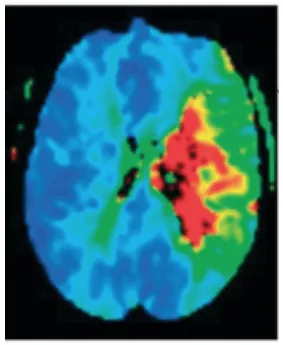

Neuroimaging techniques, such as cranial magnetic resonance imaging, allow confirmation and localization of the lesion’s topography, proving highly useful in the management of the pathology. In the acute phase, the infarcted tissue can be determined thanks to diffusion sequences, as well as the quantification of tissue extent by perfusion sequences (Ustrell-Roig y Serena Leal, 2007).

The positive discrepancy between the volume of the infarct and the volume of the penumbra (mismatch) is used as a predictor of good treatment response (a positive mismatch indicates that there is a large penumbra compared to the infarcted area, which suggests that there is still potentially salvageable brain tissue). Therefore, it is of great relevance to have neuroimaging techniques that allow delineation of the infarct core and the penumbra zone to predict the patient’s prognosis and use it when making therapeutic decisions to select patients who may benefit from reperfusion treatments beyond traditional time windows (García et al., 2022) (figure 1).